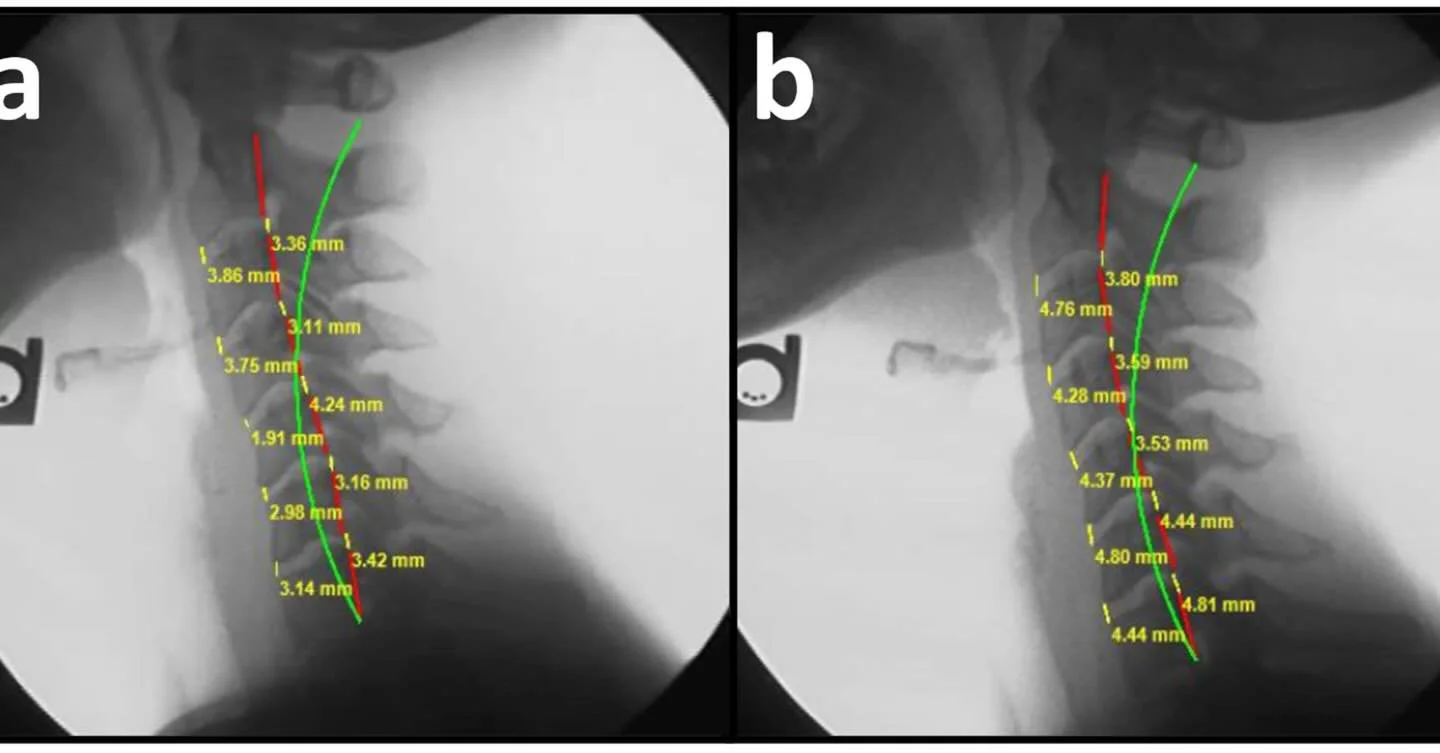

Precision Structural Correction:

Our Unique Approach to Spinal Health

At Structural Chiropractic, we don't just treat symptoms. We identify and correct the Structural Abnormalities that cause them.

We focus on Precision Structural Correction (PSC) – detecting and correcting the structural shifts in your spine that create problems throughout your body.

Structure Dictates Function

When a house's foundation moves out of proper position, the consequences throughout the structure can be severe. Wall fractures, squeaking floors, and stuck windows are merely signs pointing to the real problem: the foundation has shifted from where it should be.

Your spine works much the same way. When spinal alignment is compromised, it can trigger numerous health issues throughout your body. Treating only the symptoms without addressing Structural Abnormalities won't resolve the root problem and could allow progressive deterioration of your spine over time.